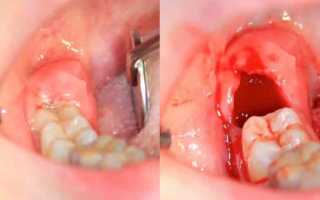

Однако, удаление зубов иногда может сопровождаться неприятными осложнениями, такими как альвеолит. Альвеолит характеризуется воспалением десны и накоплением гнойных выделений в лунке после удаления зуба. Обычно, признаки гнойного воспаления десны после удаления зуба можно заметить в течение нескольких дней.

После удаления зуба в ране образуется защитный сгусток из крови. Альвеолит, или воспаление лунки после удаления зуба, чаще всего встречается после удаления молярных зубов в нижней челюсти. Это связано с более сложной анатомией этой области, что делает хирургическое вмешательство более сложным. Кроме того, инфекция, попадая в рану, может быстро распространиться в мягкие ткани и вызвать гнойное воспаление, особенно после удаления зуба мудрости.

Скорость восстановления после удаления зуба зависит от нескольких факторов, включая физиологические особенности пациента, опыт врача, место удаления зуба и возможные осложнения операции. В некоторых случаях, когда зуб уже отсутствует или разрушается во время операции, стоматолог может прибегнуть к разрезанию десны, что может замедлить процесс заживления. После удаления зуба образуется кровяной сгусток, который играет роль барьера для защиты от инфекций. Этот сгусток необходимо оставить на месте, чтобы предотвратить воспалительные процессы. В течение нескольких дней сгусток меняет цвет и постепенно заживает, а открытая рана затягивается грануляционной тканью. Полное заживление мягких тканей обычно занимает около 2-3 недель, но процесс формирования новой костной ткани может продолжаться несколько месяцев. После удаления зуба может наблюдаться отёк десны, который обычно сходит через несколько дней.

Альвеолит: Помимо покраснения и отека лунки, обычно возникают острые боли, кровотечение и накопление гнойных выделений. Альвеолит может также сопровождаться плохим самочувствием, включая повышение температуры, дрожь, мигрени и ощущение общей слабости.